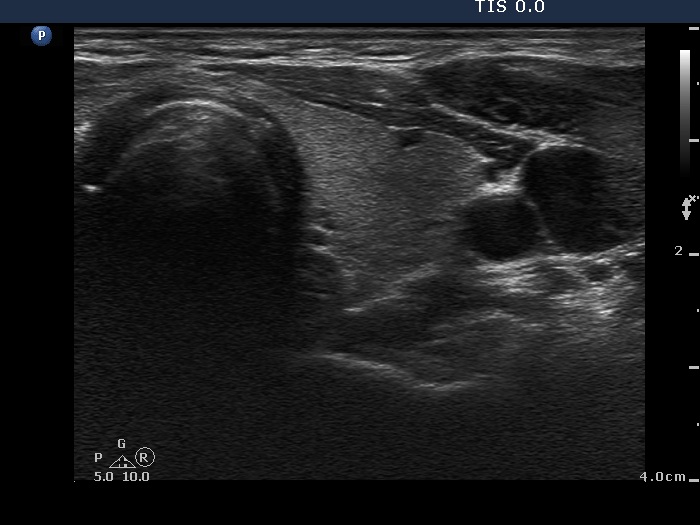

Initial examination (first row of images):

Clinical presentation: A 29-year-old woman requested a second opinion. She was in the 11th week of her pregnancy. She had mild neck discomfort for 2 months. A suspicious nodule was found in the left lobe on the evaluation. Aspiration cytology was repeatedly non-diagnostic. She was told that she had thyroid carcinoma with great probability. Her endocrinologist recommended to abort the child and then to undergo thyroidectomy.

Palpation: The left thyroid was hard on palpation, but not painful.

Ultrasonography: The right thyroid was echonormal and contained several small, insignificant lesions. There was a hypoechogenic lesion with blurred borders in the central and in the ventro-medial part of the left thyroid with increased intranodular blood flow.